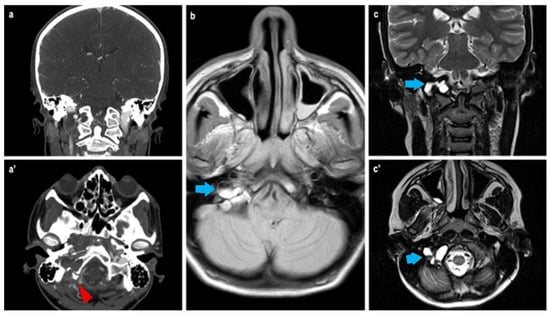

3. Case Report

| Our case report | 2025 | Italy | 1 | 14 | M | Occipital condyle | Headache, dizziness, impaired vision, and fall | No | No | Resection | 1 yr |